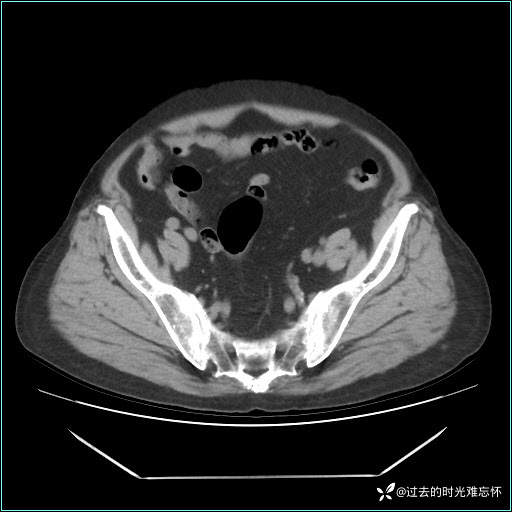

患者男,71 岁,因「反复腹痛腹胀 1 月」入院。

现病史:患者 1 月前无明显诱因下出现腹痛腹胀症状,腹痛呈隐痛,当时未予以重视,后症状有所加重,常在进食辛辣刺激油腻等食物后出现腹痛,口服药物治疗症状能得到控制,病情控制一般。现为求诊治来我院,拟“腹痛”入院。病程中患者神志清楚,精神一般,无咳嗽咳痰,无恶心呕吐,近期体重无明显变化。